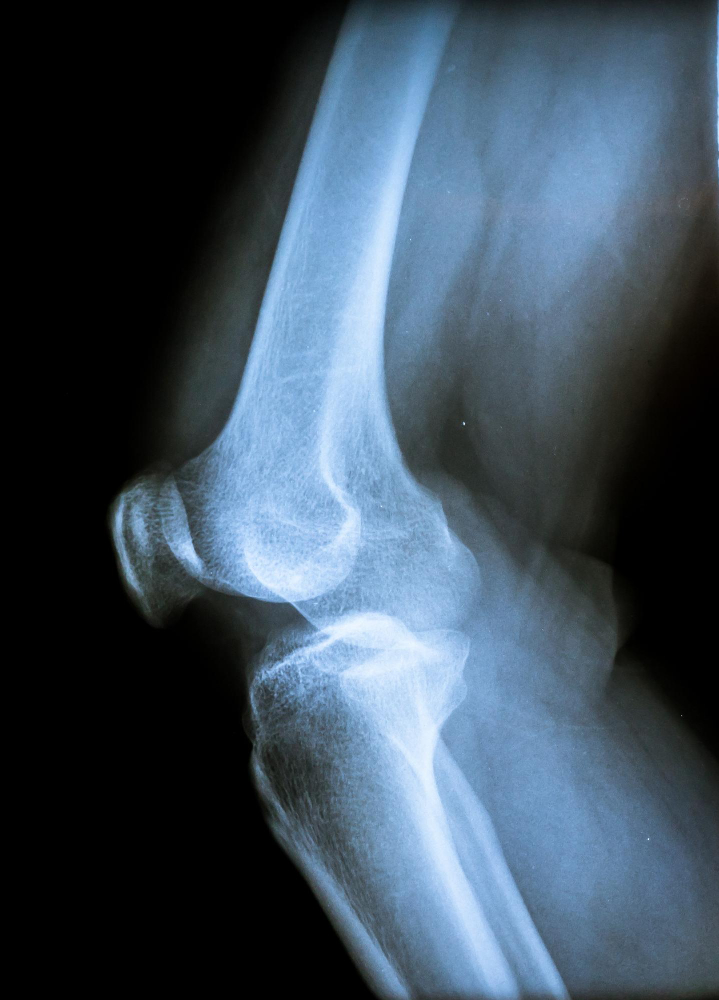

일반적인 진료와 상담, X-ray 소견으로 어느 정도 확인과 진단이 가능합니다. 물론 증상이 심하거나 만성화 되었다면 관절면의 변형이나 관절손상을 정확하게 판단하기 위해 CT, MRI 등으로 진단할 수도 있습니다.